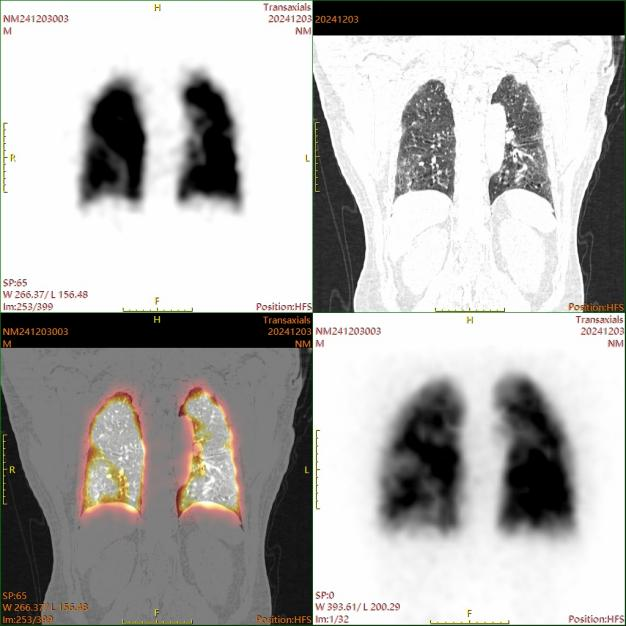

典型病例

核医学肺灌注平面显像+SPECT/CT断层融合显像示双肺多发肺栓塞。

图片